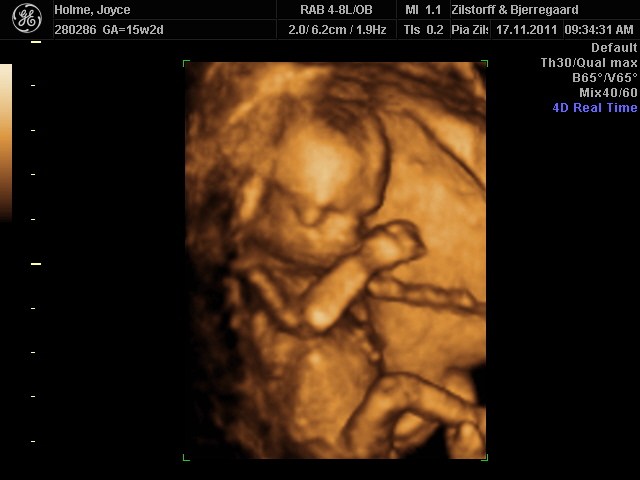

Og sikke en oplevelse, vores lille Filucca lå dog bare og sov som en sten hehe, men vi fik da lige et enkelt gab inden vi sluttede

Her er lige et par billeder af vores lille babypige